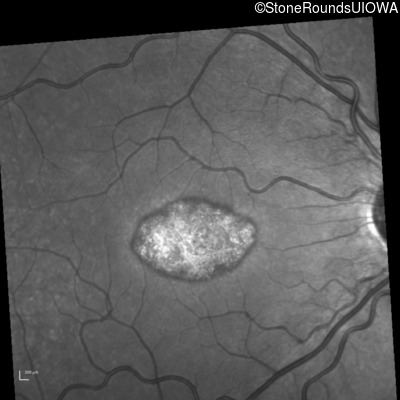

Infrared Fundus Photograph - Left - 20/25 -1 sc

Exemplar